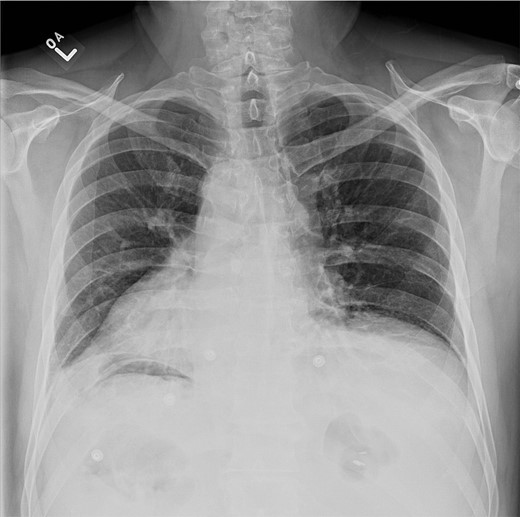

At presentation, his vitals were normal. Abdominal examination revealed an overweight gentleman with focal tenderness to the left upper quadrant. Laboratory tests revealed a WBC of 25.3 with neutrophils of 23.4. Hemoglobin, platelets, electrolytes and liver enzymes were within normal limits. Three views of the abdomen revealed no gross intra-abdominal pathology and no free air was reported on chest X-ray (Figs 1 and 2).

Chest X-ray showing left lower lobe opacity with a small volume of subdiaphragmatic free air.